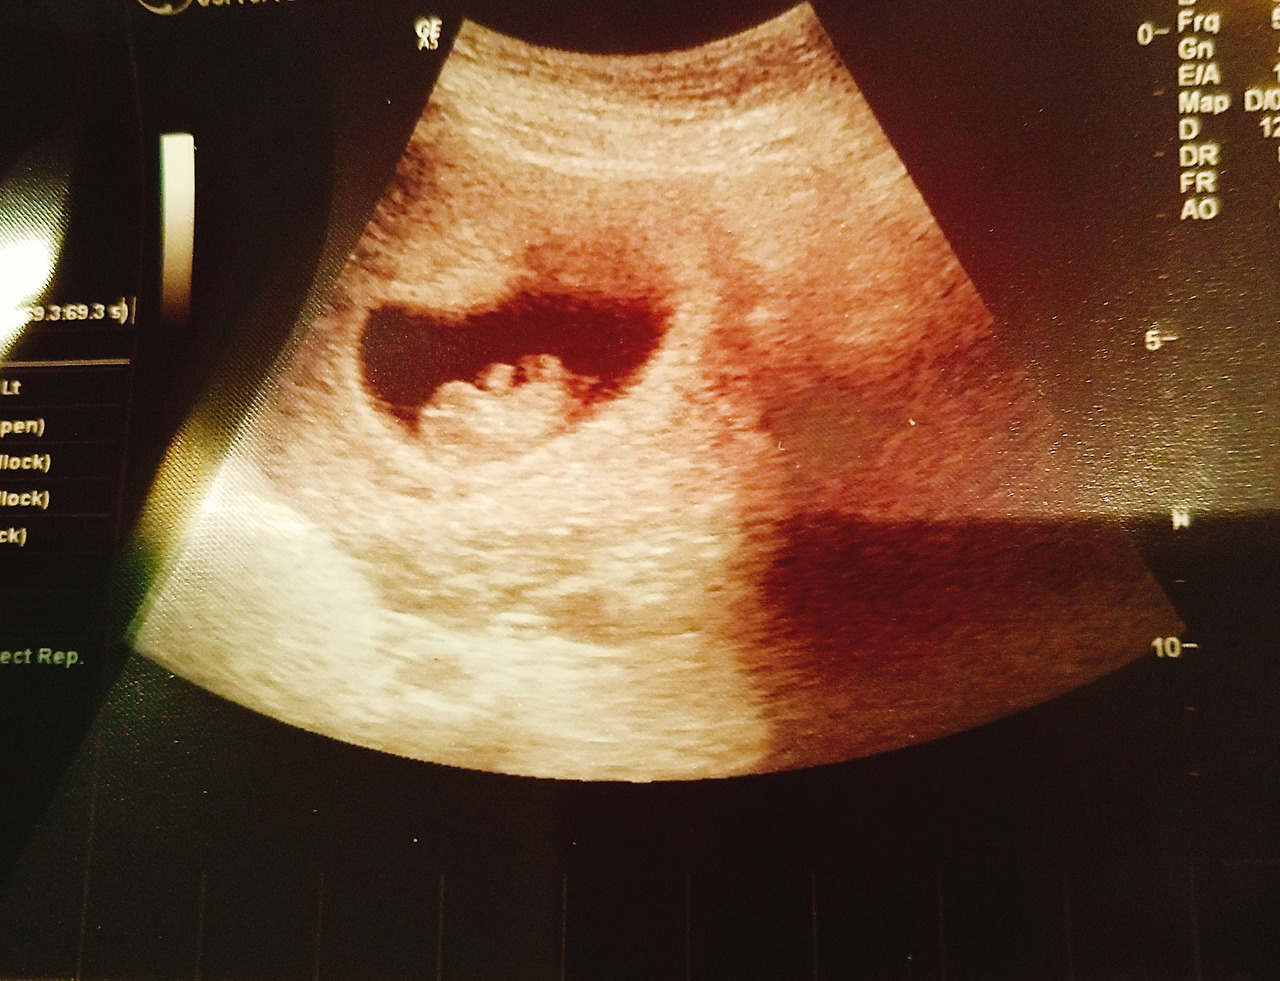

복부 초음파를 하기 전에도 의사는, 내가 지난번 응급 상황으로 병원에 왔던 것을 알고 있고 그때의 진료 기록을 다 보았는데 아이의 상태가 아주 좋더라, 그래도 오늘도 복부 초음파로 한번 더 확인해 보자, 하며 내 상황에 대해 본인이 충분히 인지하고 있다는 믿음을 가득 심어주었다. 지난번엔 응급 상황에서의 진료여서 그랬는지 초음파 사진을 출력해 주거나 하지는 않았었는데, 이번에는 다행히 가장 잘 나온 초음파 사진을 출력해 주어 받아올 수 있었다.

2018-05-19-20-34-27.jpg 아직은 뭐가 뭔지... 처음으로 받아 본 초음파 사진